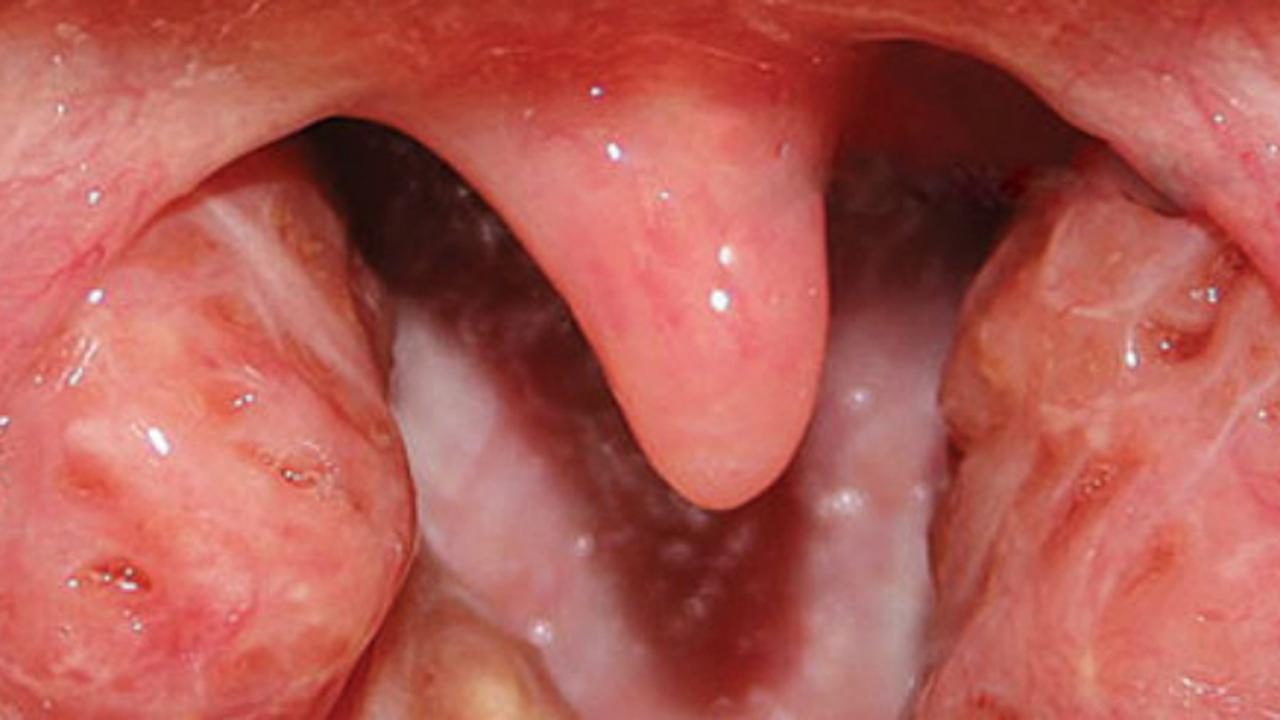

Ahli bedah, Melinda Ratini, DO, MS mengataka, amandel merupakan bagian dari sistem kekebalan tubuh Anda yang menjebak kuman masuk ke tubuh melalui mulut atau hidung Anda. Namun organ ini bisa bengkak atau infeksi.

"Orang dewasa yang perlu menjalani operasi biasanya mengalami sakit tenggorokan selama satu sampai tiga tahun terakhir atau mengalami radang tenggorokan oleh infeksi paling sedikit tiga bulan," katanya.

Alasan lain mengapa orang dewasa perlu operasi amandel adalah risiko munculnya penyakit lain seperti sleep apnea obstruktif (penyumbatan saluran napas bagian atas), bau mulut yang tidak hilang serta kanker.